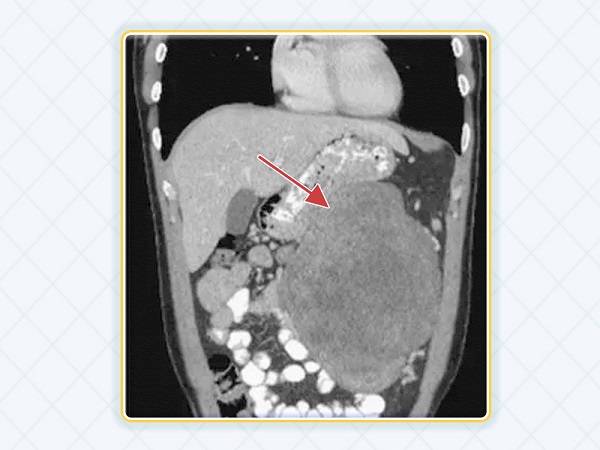

胃肠道间质瘤多发生在胃、小肠、直肠等部位,少部分也可能出现在胃肠以外的地方,比如腹腔。

刚开始发现都是通过影像学,比如CT、B超、磁共振,看到体内长个东西。还有一种情况是通过胃镜,发现胃里、肠道里长了东西。但是这些检查都是辅助检查,不能做出明确诊断,需要进一步取活检做病理检查,病理检查是诊断胃肠道间质瘤的金标准。

胃肠道间质瘤最重要的并发症是出血,因为胃肠道间质瘤自己可以生成新生血管,血液供应很丰富,在外力作用下,或者生长速度过快时,可能会自发性破裂,造成大出血,止血不及时可能会危及生命。

肿瘤长大后可能会压迫周围脏器,比如压迫肠道、泌尿系统,造成肠梗阻和泌尿系梗阻,可能会导致脏器衰竭,给患者生命带来威胁。